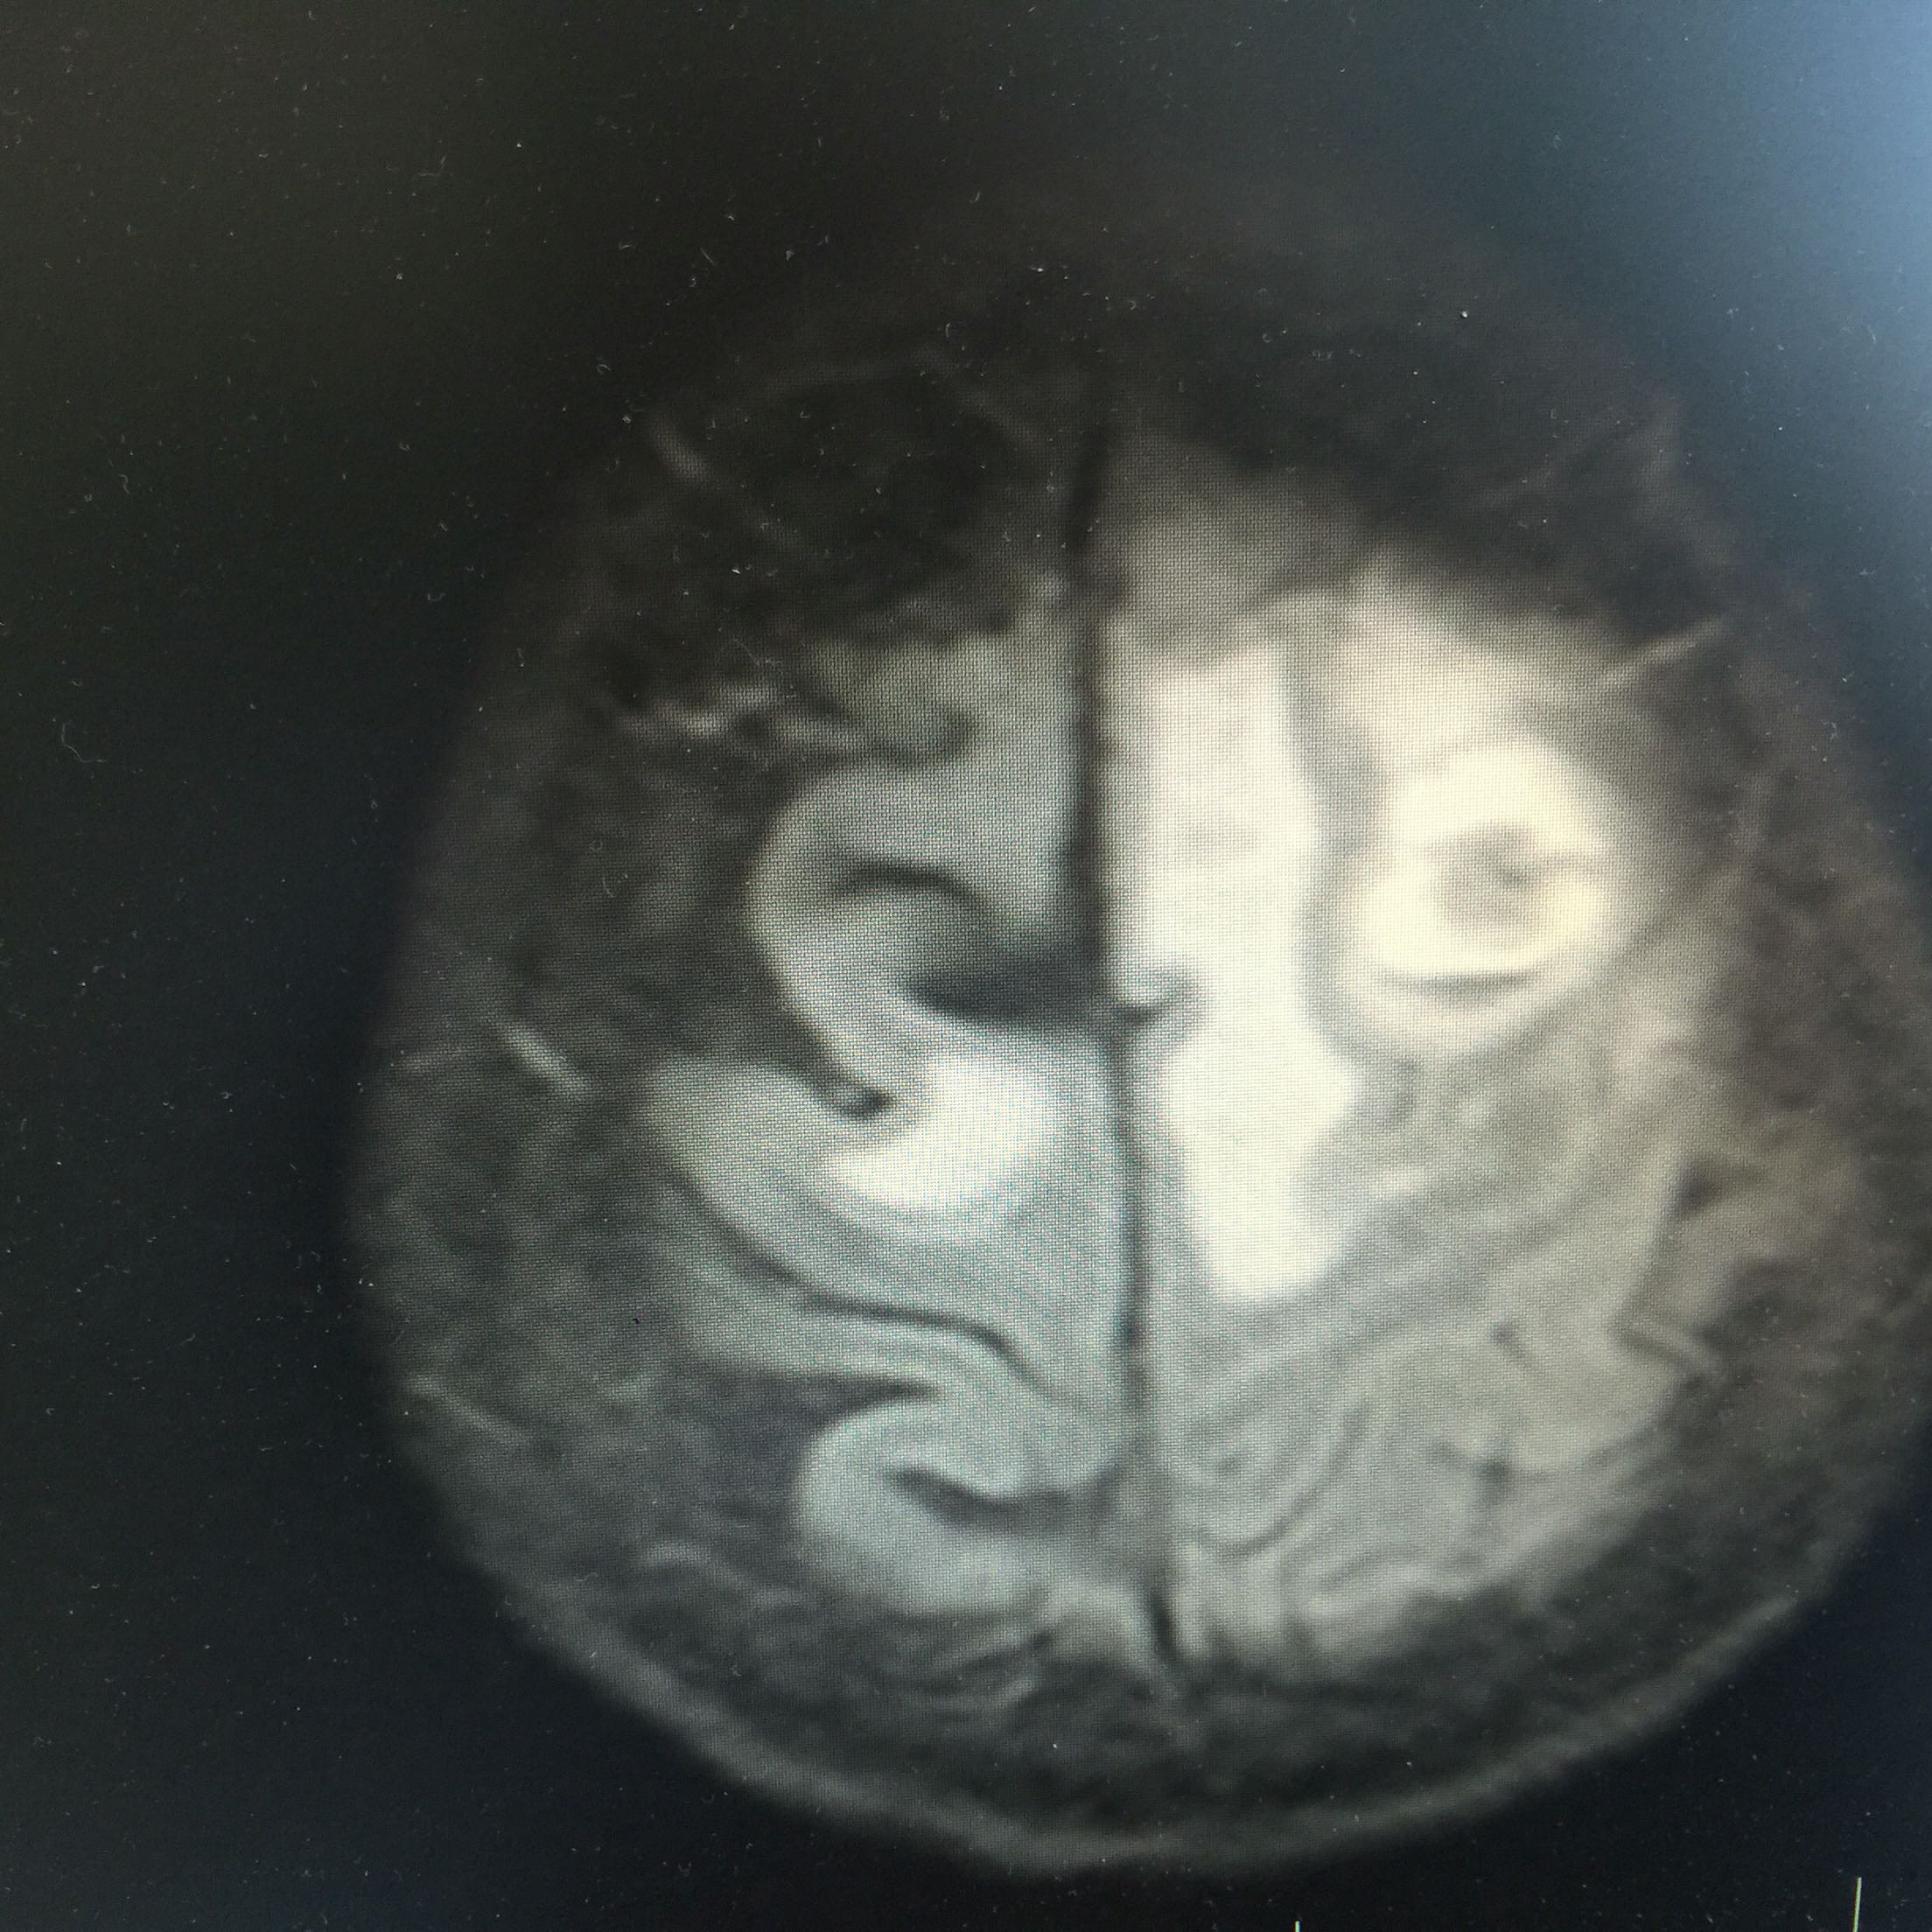

1.女,81岁,以“右侧肢体无力3天”入院。 2.现病史:3天前无诱因出现右侧肢体无力,右上肢抬举费力,右下肢步行拖拉,无抽搐,无意识障碍! 3.既往史:2016年肺穿刺活检,免疫组化为腺癌!已合并第五、六椎体转移、左肾上腺转移,行灌注介入治疗。

查体:血压:130/80mmHg,两肺呼吸音清,未闻及啰音,心率98次/分,律齐,未及杂音,双下肢无水肿。神经系统查体:意识清,双侧瞳孔等大正圆,直径约3.0mm,对光反射灵敏,无面舌瘫,右侧肢体肌力4级,腱反射减弱,Babinski征R+L-。

左肺腺癌 骨转移、双肺门及纵膈淋巴结转移、左肾上腺转移、脑转移! 治疗:对称、支持治疗!